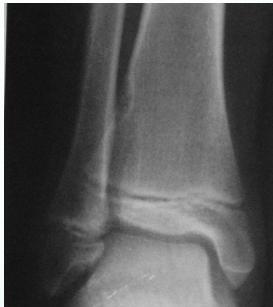

Giant-Cell Tumor

- Unknown origin:

- Giant cells abundant

- Behavior:

- One third benign

- One third locally aggressive

- One third (less) with distant metastasis

- Young adults

- Common sites:

- Around knee

- Proximal humerus

- Distal radius

Radiological Features

- Eccentric lesion:

- Radiolucent

- Soap bubble

- Abuts (adjacent) against the joint

- Thin cortex

- Margins may be clear / unclear:

- Depends on aggressiveness

- Treatment:

- Curettage & bone grafting

- More wide excision in recurrent and aggressive lesions